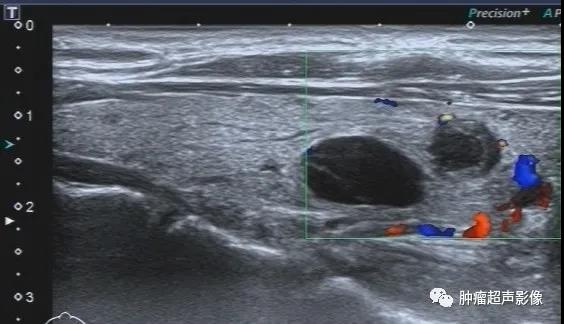

甲状腺下极结节,病史不明,呈低回声,边缘光整,呈双环征(周边低回声晕),内部无血流,采用超微血流成像显示内部无血流,呈“黑洞征”,从而增加诊断皱缩结节的信心,避免穿刺及手术。